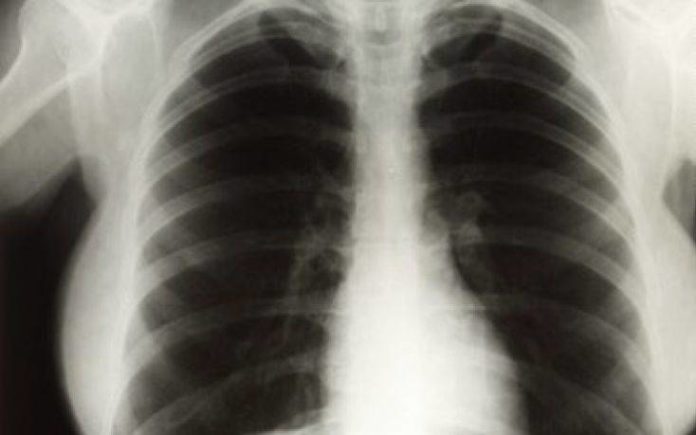

Ένα νέο σύστημα τεχνητής νοημοσύνης της Google Health, θυγατρικής της Google στο πεδίο της «έξυπνης» υγείας, μπορεί να μελετήσει ακτινογραφίες πνευμόνων και να βγάλει συμπεράσματα εξίσου αξιόπιστα με εκείνα των έμπειρων ακτινολόγων. Το σύστημα βαθιάς μάθησης της Google, σύμφωνα με τους δημιουργούς του, μπορεί να αποτελέσει πολύτιμο βοηθό των γιατρών στο μέλλον.

Οι ερευνητές, που έκαναν τη σχετική δημοσίευση στο περιοδικό «Radiology» της Ακτινολογικής Εταιρείας της Βόρειας Αμερικής, εκπαίδευσαν το σύστημά τους τροφοδοτώντας το με περισσότερες από 860.000 ακτινογραφίες. Η ακτινογραφία πνευμόνων είναι από τις συχνότερες εξετάσεις παγκοσμίως, όμως έχει ορισμένους περιορισμούς.

Οι δοκιμές του συστήματος από επιτροπή ακτινολόγων έδειξαν ότι τα καταφέρνει τουλάχιστον εξίσου καλά με τους γιατρούς στην ανίχνευση διαφόρων προβλημάτων (διάγνωση καταγμάτων, οζιδίων, όγκων, πνευμοθώρακα κ.ά.).